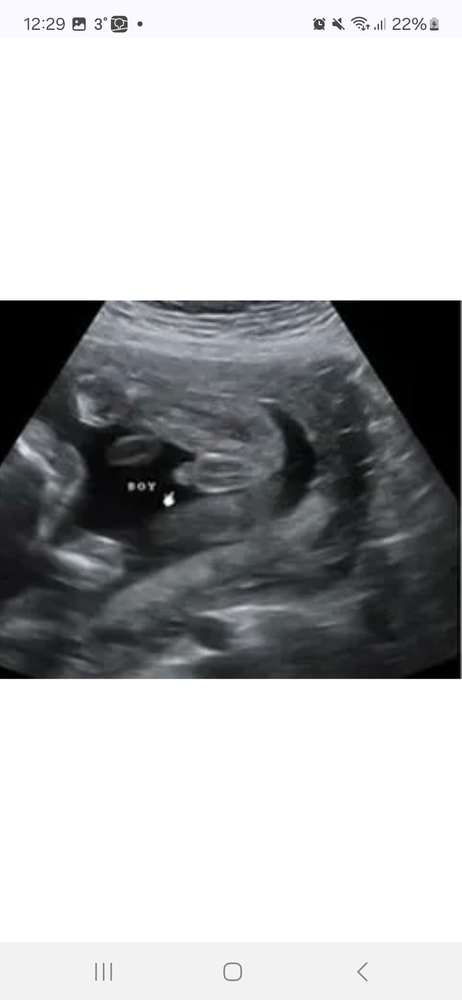

Маша, примеры Изображение Примеры из интернета,мне кажется ваш случай девочка Изображение

10.11.2025

Маша, у меня на каждом узи уже смотрели ) вот так было в 20 недель мальчиком и не пахло Изображение

09.11.2025

Татьяна, ну да у вас четко видно ))